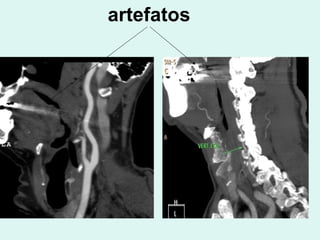

artefatos

O posicionamento deveser Planejado, de modo a evitar que os artefatos, principalmente metálicos atrapalhem a imagem

Posicionamento correto,com hiperextensãodo pescoço, evitando sobreposição de artefatos metálicos na região das carótidas